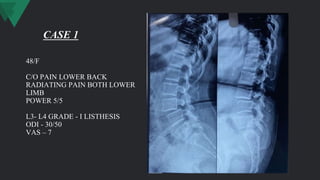

48/F

C/O PAIN LOWER BACK

RADIATING PAIN BOTH LOWER

LIMB

POWER 5/5

L3- L4 GRADE - I LISTHESIS

ODI - 30/50

VAS – 7

CASE 1